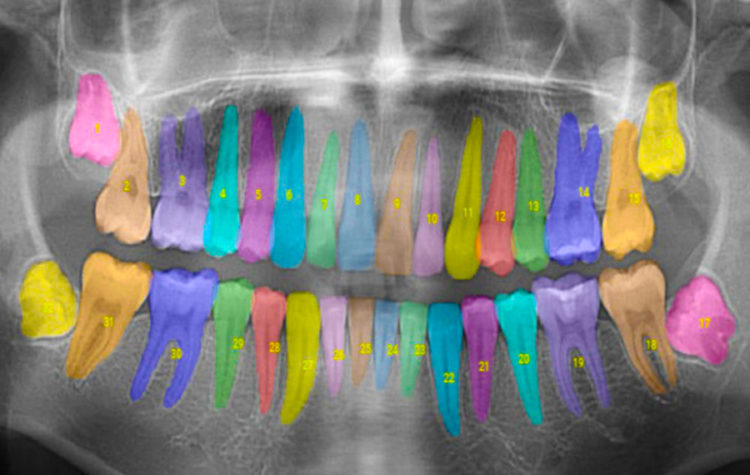

MIT alumni-founded Overjet analyzes and annotates dental X-rays to help dentists offer more comprehensive care.